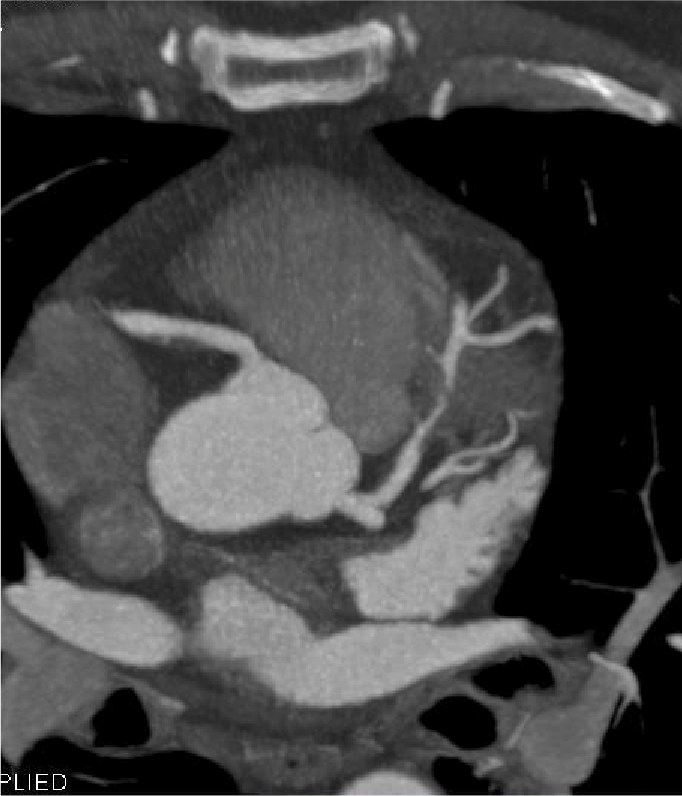

Tomografía cardiaca

Este estudio es adquirido con un tomógrafo de alta velocidad y baja radiación que permite evaluar las arterias coronarias y demostrar la ausencia o la presencia de placas ateromatosas, que son las que ocasionan un infarto (enfermedad arterial coronaria). Mediante la emisión de rayos X es posible obtener imágenes bidimensionales y tridimensionales del exterior y del interior de las arterias coronarias, del corazón y de la función cardiaca.

Una modalidad de la tomografía cardiaca muy utilizada hoy día es el índice de calcio coronario que es útil para identificar oportunamente la presencia de calcio que se asocia con las placas de ateroma que obstruyen tus arterias y ocasionan un infarto. Este estudio se adquiere en menos de un minuto y no se necesita utilizar medio de contraste.

El calcio que se deposita en las arterias coronarias es la “primera señal” que podemos medir antes de que aparezcan los síntomas de la enfermedad y en conjunto con las indicaciones de tu médico, podrás prevenir la progresión de la enfermedad e incluso un infarto.

Cuando es necesario hacer una evaluación mas precisa de tus arterias coronarias la tomografía cardiaca permite, mediante la inyección de contraste por una vena del brazo, estudiar el interior de las arterias y demostrar si existen o no placas que impiden el paso de sangre hacia el corazón, a esta modalidad de la tomografía cardiaca le conocemos como angiotomografía coronaria, que se adquiere en 30 a 60 minutos, y es hoy día el estudio mas confiable para evaluar en forma no invasiva las arterias que nutren al corazón y que cuando se enferman pueden ocasionarte un infarto.

Existen otras indicaciones de la tomografía cardiaca que permiten evaluar las válvulas del corazón y de los grandes vasos como la aorta.